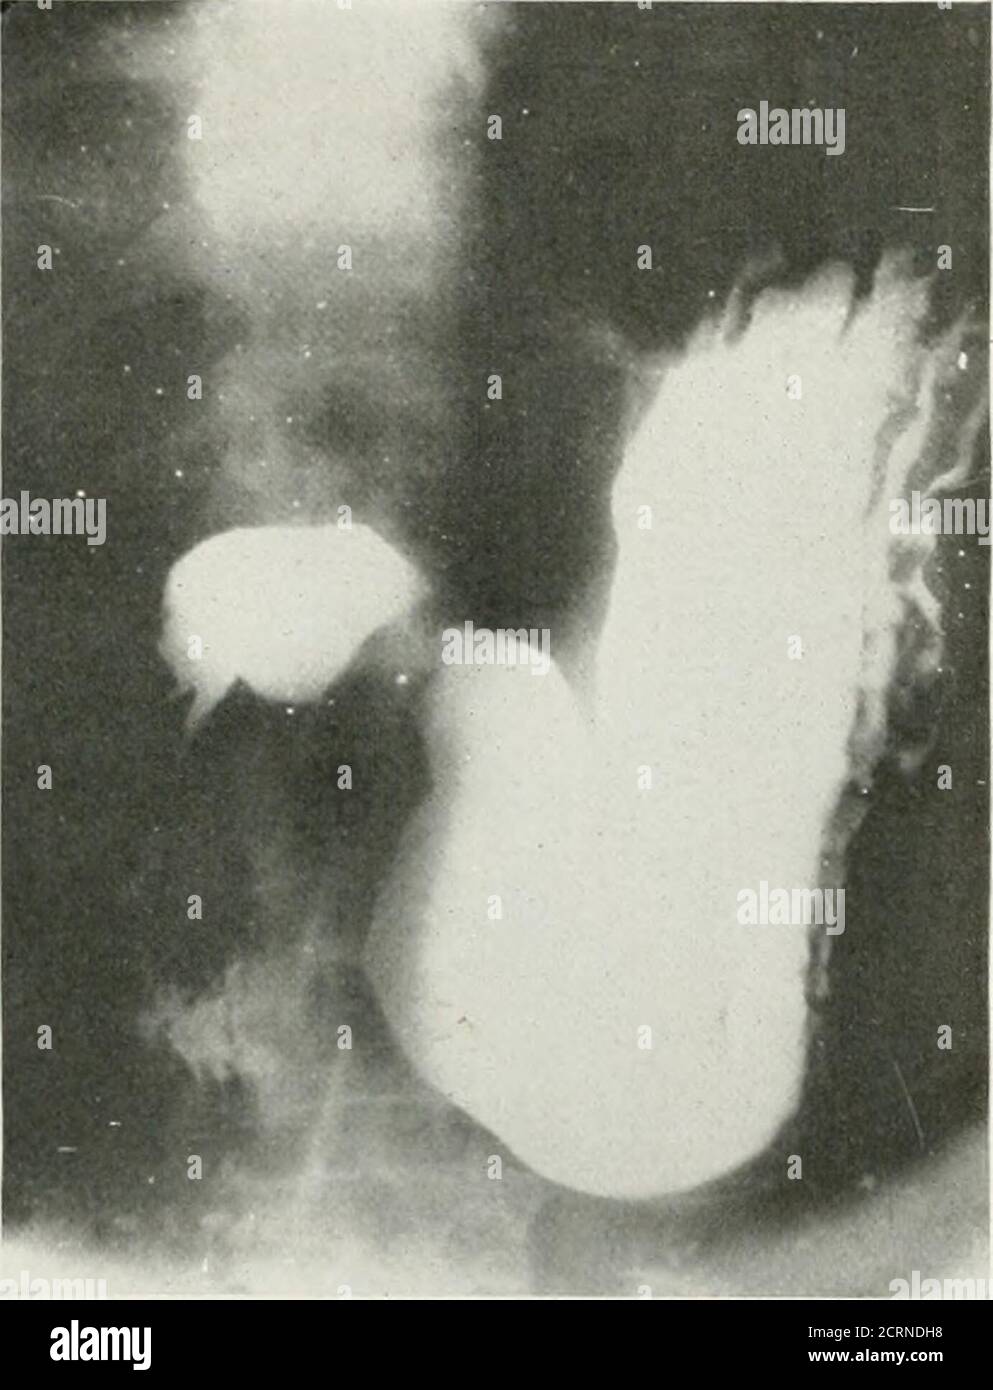

From www.alamy.com

Medical imaging radiological examination with barium enema following a Barium Enema Nuclear Medicine These doses can be compared. Average effective dose for most nuclear medicine procedures varies between 0.3 and 20 msv. A barium enema is an examination of the colon (large bowel) and rectum of the lower gastrointestinal (gi) tract. It uses a contrast substance to coat. A substance called barium is used to make your bowel show up more clearly. The. Barium Enema Nuclear Medicine.